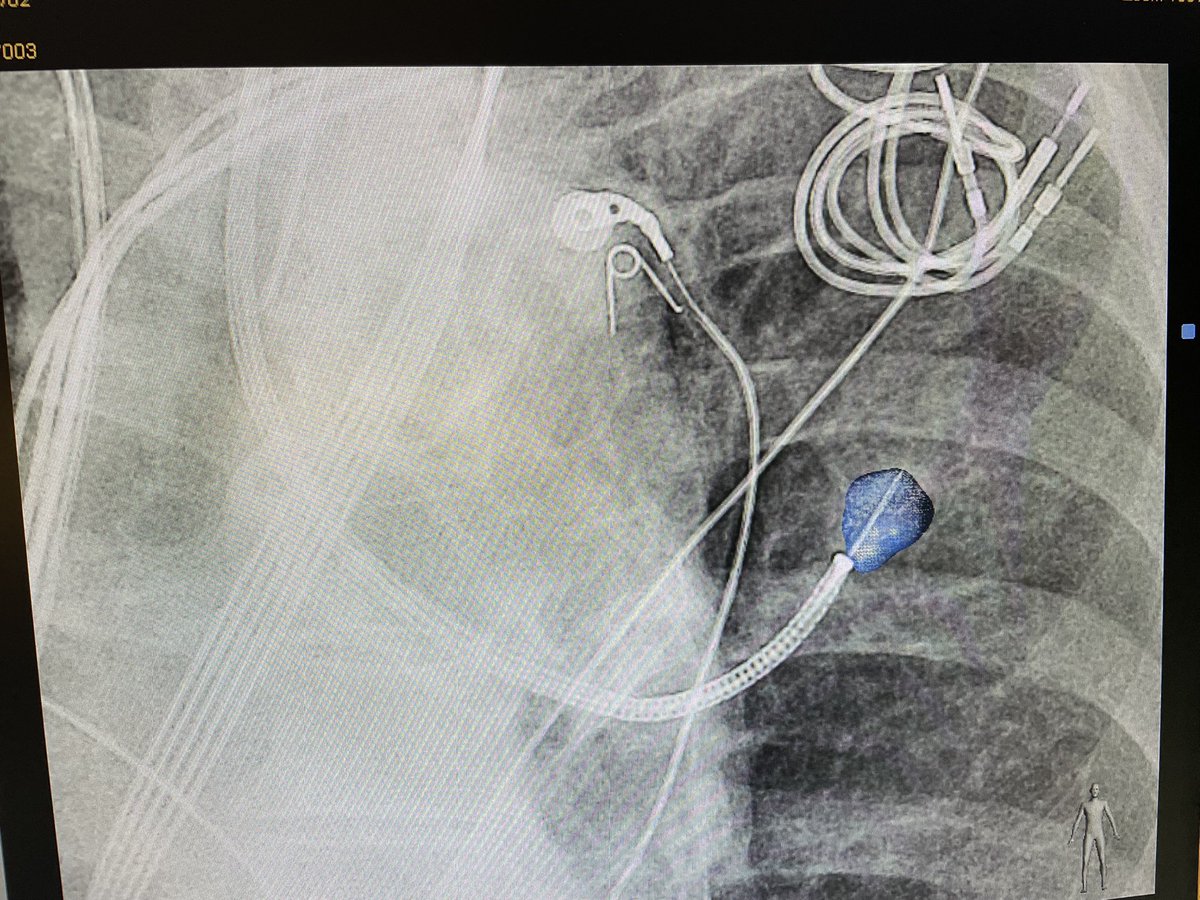

Ramsy Abdelghani, MD@Rabdelgh·

Growing LUL pleural based lesion with no airway leading to it and negative on IR biopsy. Was able to navigate close (within 2cm) to the lesion, biopsy, and adjust using CBCT. Positive for poorly differentiated carcinoma. I would have never tried this without CBCT and Robotics.